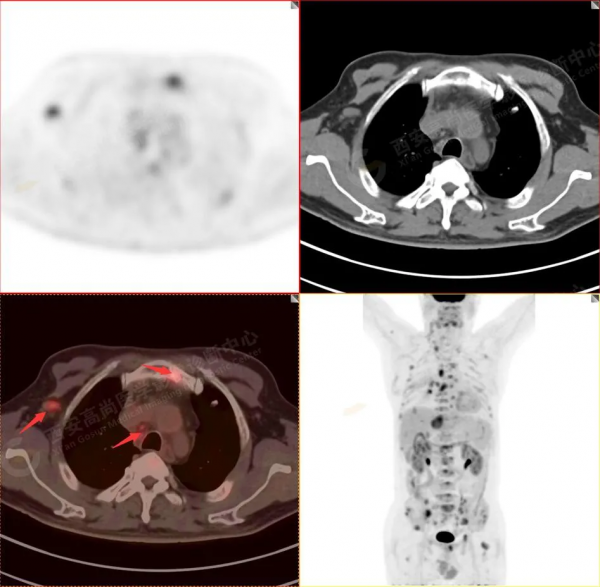

1.以下為肺內原發灶

1.右肺下葉後基底段軟組織結節(約1.5cm×1.2cm),與相鄰後胸膜分界不清,呈FDG代謝異常增高,結合病理,符合肺腺癌伴鄰近胸膜侵犯。

2.雙肺多發高密度小結節灶(最大徑約0.7cm),部分較大結節呈FDG代謝略增高,均考慮為轉移性病變。

3.右側肺門、縱隔(1L、1R、3A、4、6、7組)及雙側鎖骨上多發腫大淋巴結,呈不同程度FDG代謝異常增高,考慮為淋巴結轉移。

4.右後胸膜輕度增厚,形成多個條狀軟組織病變,呈FDG代謝輕度異常增高,考慮為轉移性病變;右側胸腔微量積液。

5.腰4椎體左側緣溶骨性骨質破壞,FDG代謝異常增高,考慮骨轉移瘤。

6.肝內小結節,考慮轉移可能性大,建議MR增強掃描。

以上病變符合:T4N3M1c,ⅣB期(UICC/AJCC,2018年第8版肺癌TNM分期)。